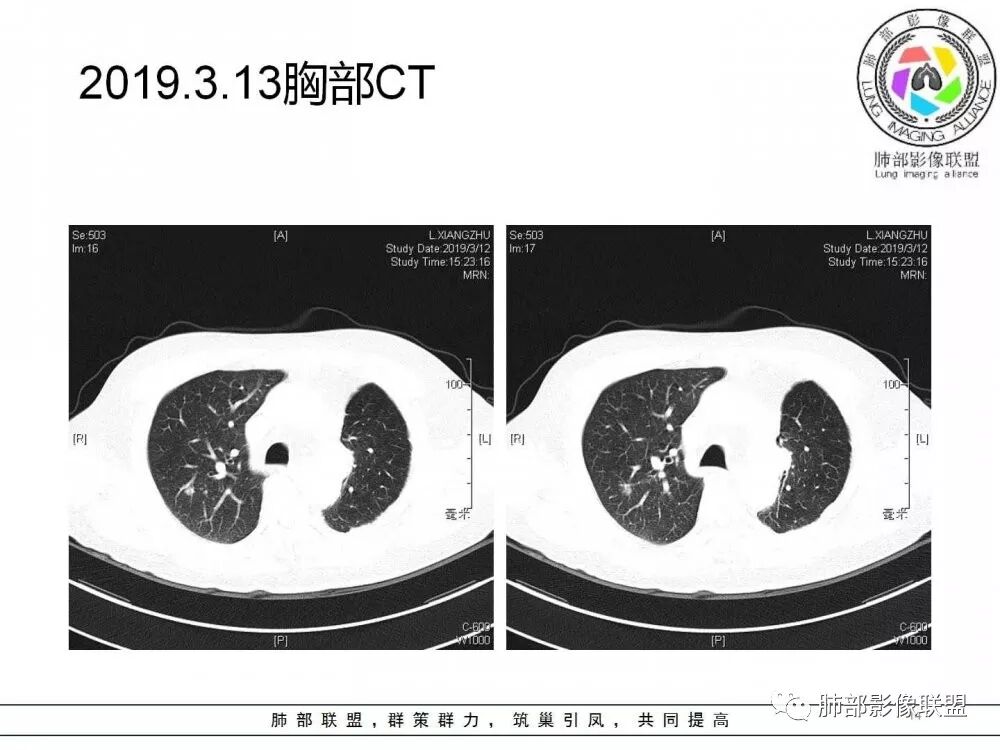

右肺上叶后段实性结节,部分边缘磨玻璃,周围可见多发小结节,病灶逐渐进展,临床有肺癌病史、LGG4相关病变、激素长期使用史,考虑1隐球菌。2肺癌复发。3LGG4相关性肺改变,病变局限,应该不符合。

右肺上叶后段多发实性结节,边缘收缩,葫芦兄弟,临床有激素治疗史,考虑隐球菌。

肺癌病史,长期激素实用史,IgG4相关病史,治疗有抗癌和激素治疗,肺部多发胸膜下小结节,边缘模糊,有些结节有进展,葫芦兄弟,考虑隐球菌。

右肺上叶后段实性结节,周围可见多发小结节,病灶逐渐进展,临床有肺癌病史、LGG4相关病变、激素长期使用史,考虑1隐球菌。2肺癌复发。3LGG4相关性肺改变

病例1右肺上叶后段实性结节,部分边缘磨玻璃,周围可见多发小结节,病灶逐渐进展,临床有肺癌病史、LGG4相关病变、激素长期使用史,考虑1隐球菌。2肺癌复发。3LGG4相关性肺改变,病变局限,应该不符合。(临床小白,纯属蒙)

病灶从2月份就开始有,应该最早说是1月7号就有了,到3月13号稍微增大一点,到后面几乎没变化,到5月份好像稍微大一些,炎性应该是炎性,犹豫的是这个炎性到底什么病变呢?其实本没变化,它特点一个是在叶裂上,跟血管关系密切,但是病灶边缘稍收缩,病灶没有太大变化。

因为这个长轴似乎跟支气管走行一致的,其实治疗效果不是很理想,我先把性质定为炎性。因为这个病灶它沿着血管支气管走行的方向,大家都考虑隐球菌,这么久病灶无明显变化,它跟血管束关系很密切。我犹豫就在此,到底是IgG4还是隐球,大方向是炎性,不符合的就是也在激素治疗。